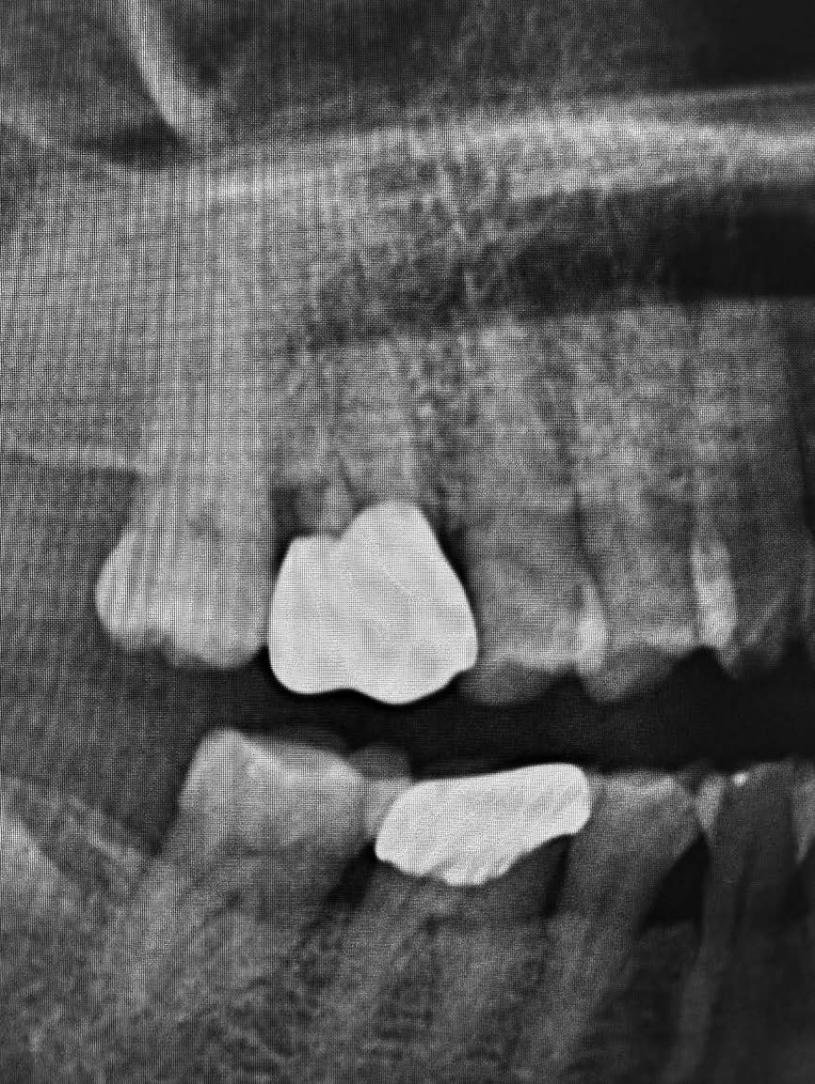

(工商新聞)「Yomi牙科機器人3D導航系統」不但提供精準牙齒及頜骨的重要資訊,可以協助牙醫制定完美的植牙計劃,並幫助牙醫完成該計劃。

Yomi是全球第一也是唯一的植牙機器人,全新科技能確保植牙的準確性,這包括植入物的類型、大小及位置 ;並且減少植牙手術的創傷疼痛、感染風險和快速恢復。

6.斥資引進「YoMi 牙科機器人3D導航系統」,可以拹助牙醫制定完美的植牙計劃,並幫助完成計劃。